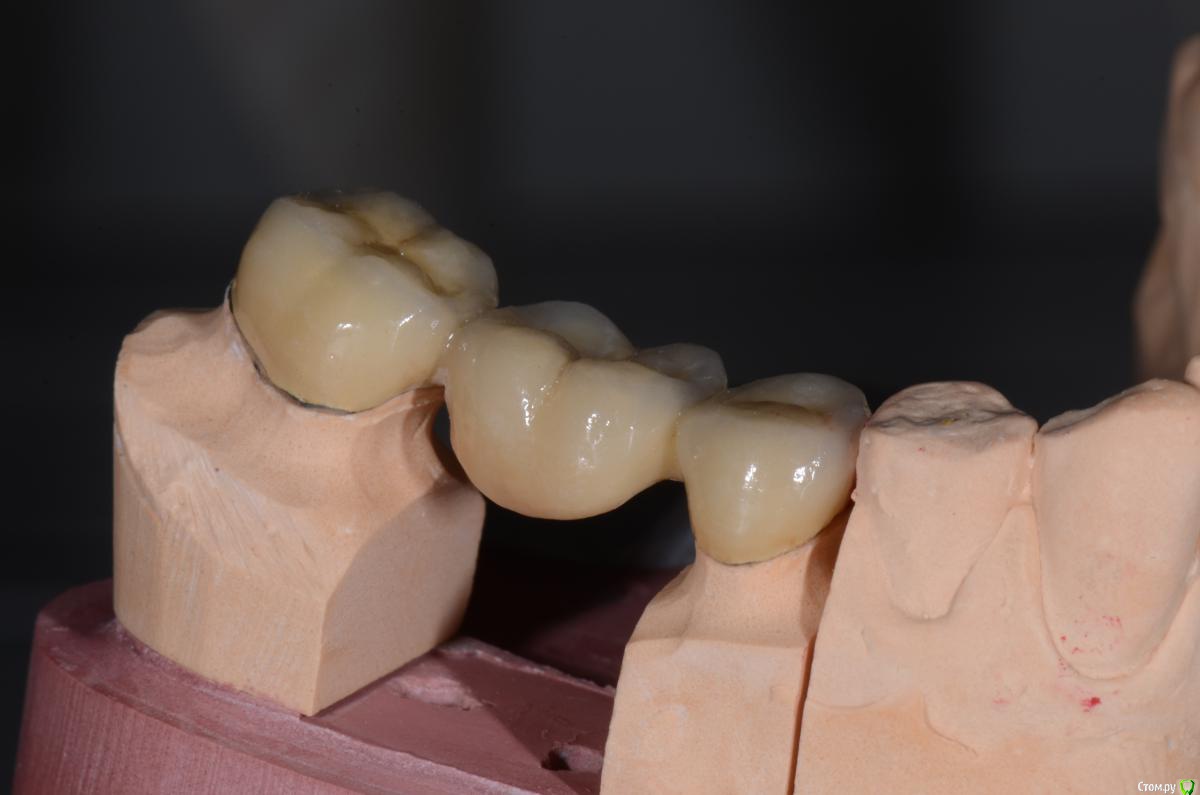

DimaKoleso Опубликовано 23 января, 2016 Поделиться Опубликовано 23 января, 2016 Решил выбросить на всеобщее обозрение вот такую работу. Ваше мнение? Делаете ли Вы гирлянду? В данном случае 47 зуб гирлянда 360, 45 зуб гирлянда 180 6 Ссылка на комментарий

krokomot Опубликовано 23 января, 2016 Поделиться Опубликовано 23 января, 2016 Моделировка слабая, группового ведения не будет еще и три зуба Ссылка на комментарий

DimaKoleso Опубликовано 23 января, 2016 Автор Поделиться Опубликовано 23 января, 2016 Моделировка слабая, группового ведения не будет еще и три зубаАнтагонисты заканчиваются на 5ке, поэтому про групповое ведение забыть можно. Ссылка на комментарий

Карен Аванесов Опубликовано 25 января, 2016 Поделиться Опубликовано 25 января, 2016 Широко для гирлянды. Техник хорошо постарался. Ссылка на комментарий

DimaKoleso Опубликовано 26 января, 2016 Автор Поделиться Опубликовано 26 января, 2016 Широко для гирлянды. Техник хорошо постарался.Да, мой косяк( Ссылка на комментарий

Карен Аванесов Опубликовано 28 января, 2016 Поделиться Опубликовано 28 января, 2016 (изменено) Много, зуб меньше точить, прилегание лучше, гнить зуб не будет, ну и вообще оригинально смотрится. Изменено 28 января, 2016 пользователем Карен Аванесов Ссылка на комментарий